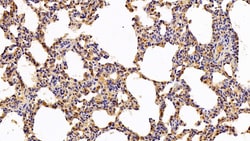

Ionized calcium-binding adapter molecule 1 (IBA1), also known by its gene name AIF1, is a protein expressed predominantly by microglia in the brain and spinal cord. This protein belongs to the EF-hand calcium-binding protein family and plays a crucial role in microglial activation and migration in response to brain injury or neuroinflammation. IBA1's function is integral to microglial motility and phagocytic activity, facilitating the cellular response to pathogenic stimuli and promoting tissue homeostasis and repair in the central nervous system. IBA1 serves as a reliable marker for activated microglia in various neurological disorders, including Alzheimer's disease, Parkinson's disease, and multiple sclerosis, where increased expression correlates with disease progression and severity. The protein's structural features enable it to bind calcium ions, inducing conformational changes that activate signaling pathways essential for microglial function. Its expression is highly regulated by inflammatory cytokines, underpinning its role in neuroimmune responses. Due to its specific expression in microglia during pathological conditions, IBA1 is widely used in research as a marker to study microglial status and activity, and it remains a focal point for understanding microglial involvement in neurodegenerative diseases.Specifications

| Immunohistochemistry (Paraffin), Western Blot | |